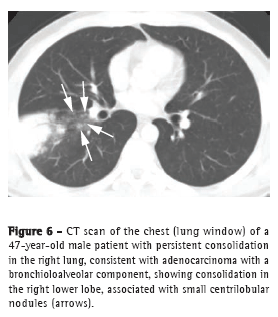

The consolidation pattern accounts for up to 30% of all BAC cases, being more common in the mucinous variant.(3) This pattern has also been described as the pneumonic form of BAC.(18) Given the difficulty in distinguishing this BAC pattern from that of infectious pneumonia, there is often a delay in diagnosis. Some findings, such as the angiogram sign, air bronchograms, ground-glass opacities, and air-space nodules (Figure 6), can be observed in BAC and in lobar pneumonia.(3,19) Lymph node enlargement and pleural effusion can also be found in both entities.(16) Parenchymal consolidation that remains unresolved after treatment should raise the hypothesis of lung cancer.(2,3,18)